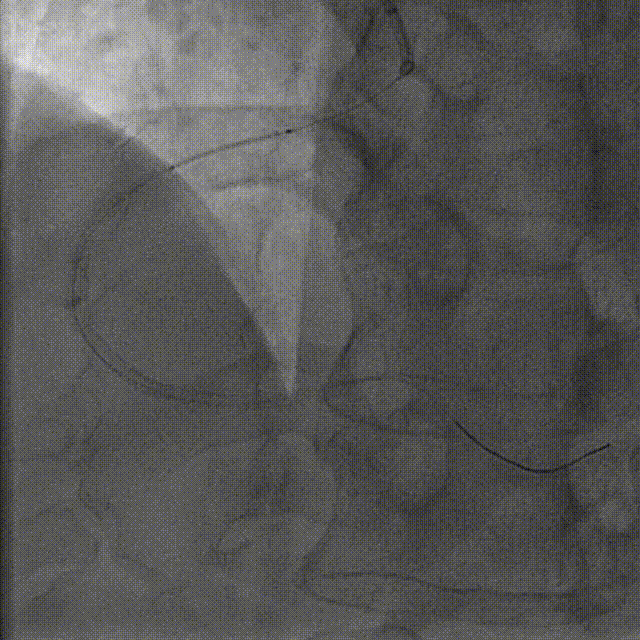

冠脉造影:左主干管壁钙化,末段狭窄约20%,回旋支远段100%闭塞,顿缘支近段狭窄约90%。

冠脉造影:前降支近段管壁钙化狭窄约50%,右冠脉开口变异管壁钙化,近段至远段弥漫病变狭窄约70%-90%。

本病例的特点:左主干合并三支病变,首先处理右冠脉病变。因右冠脉开口于左窦,冠脉管壁钙化,且病变弥漫,选择容易到位的指引导管,术中尽可能早期应用导引延长导管辅助完成手术。